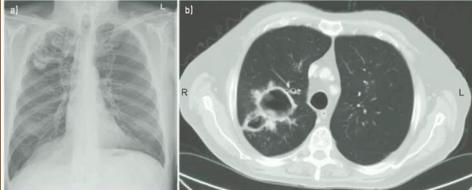

1、胸部影像学(CT最佳)符合CPA表现;

2、血清学:直接依据(培养到曲霉菌)+间接依据(GM试验、G试验、曲霉菌抗体检测、沉淀试验),排除其他诊断(结核、肿瘤);